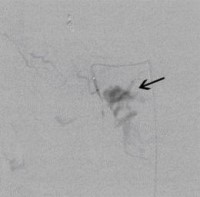

Postoperative abdominelle Blutungen bei chronischer Pankreatitis nach Embolisation der Art. gastroduodenalis mittels Metallspiralen (Coils)

(Bild 3 von 5)